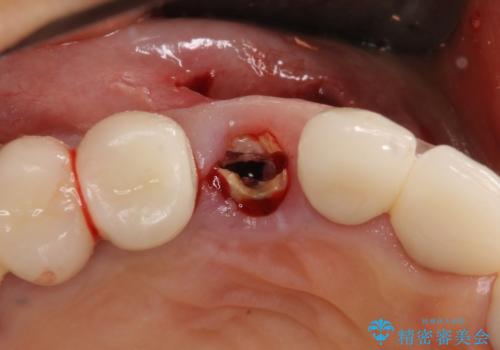

他の部位にインプラント治療を行っていたことから、こちらの歯に対してもインプラントによる補綴治療を希望されたため、1泊での帰国時に抜歯、インプラント埋入、仮歯の装着を行い、数ヶ月後の帰国時にオールセラミッククラウンの型取りと装着を行う計画としました。

インプラント埋入時は1泊、補綴治療時には3週間ほど日本に滞在していただき、2回の渡航で無事に治療を終えることができました。